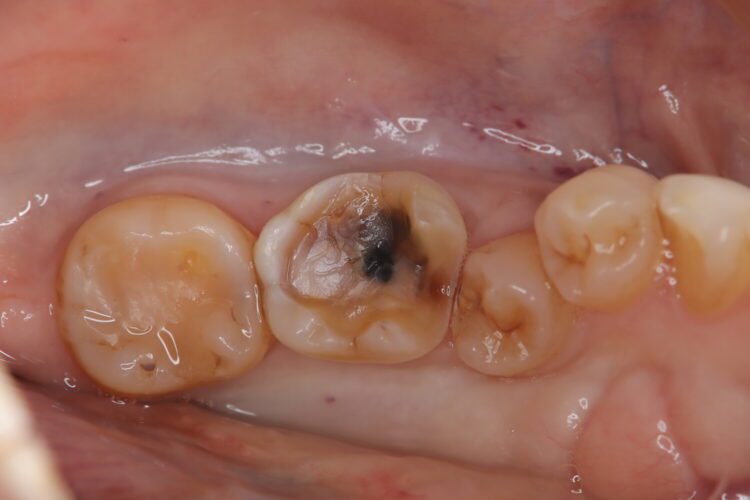

1段目口腔内写真 中央

治療した歯の中央に黒い部分がありますが、これは虫歯ではなく以前の治療で使われたサホライドという虫歯の進行どめの薬による変色と考えられます。